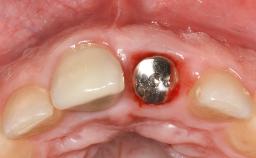

In this case, Nicola Zitzmann describes the sudden loss of a previously well-osseointegrated implant that had been in healthy function for 5 years. The case includes recommendations for occlusion and function of implant restorations. A 74-year-old patient had received implant-fixed dental prostheses in the maxilla in 2008, and in the right mandible three years later. His tooth loss was mainly related to recurrent caries associated with hyposalivation as a potential side effect of his cholesterol-lowering medication.